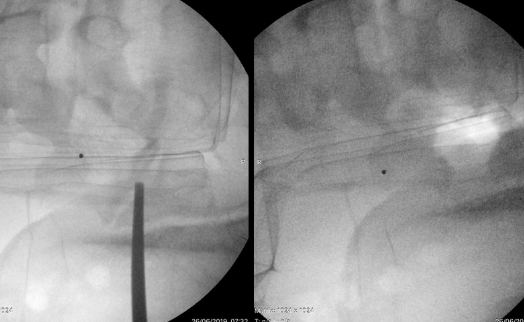

Operacja polega na wytworzeniu przestrzeni między kontaktującymi ze sobą elementami kostnymi. Za pomocą wiertarki szybkoobrotowej, dłuta i innych narzędzi chirurgicznych, rozdziela się te dwie, ocierające o siebie powierzchnie.